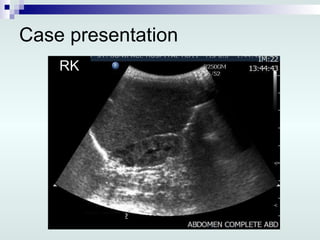

Case presentation 1 st  day of life: Abdominal and renal US: Lt multicystic dysplastic kidney, 7.3 x 4.1 x 4.8 cm Rt kidney smallish, 3.2 x 2.1 x 1.8 cm Urinary bladder is minimally distended No ascites Nephrology consultation: Renal failure Foley’s catheter VCUG

Case presentation RK

Case presentation 1st day of life: Abdominal and renal US: Lt multicystic dysplastic kidney, 7.3 x 4.1 x 4.8 cm Rt kidney smallish, 3.2 x 2.1 x 1.8 cm Urinary bladder is minimally distended No ascites Nephrology consultation: Renal failure Foley’s catheter VCUG